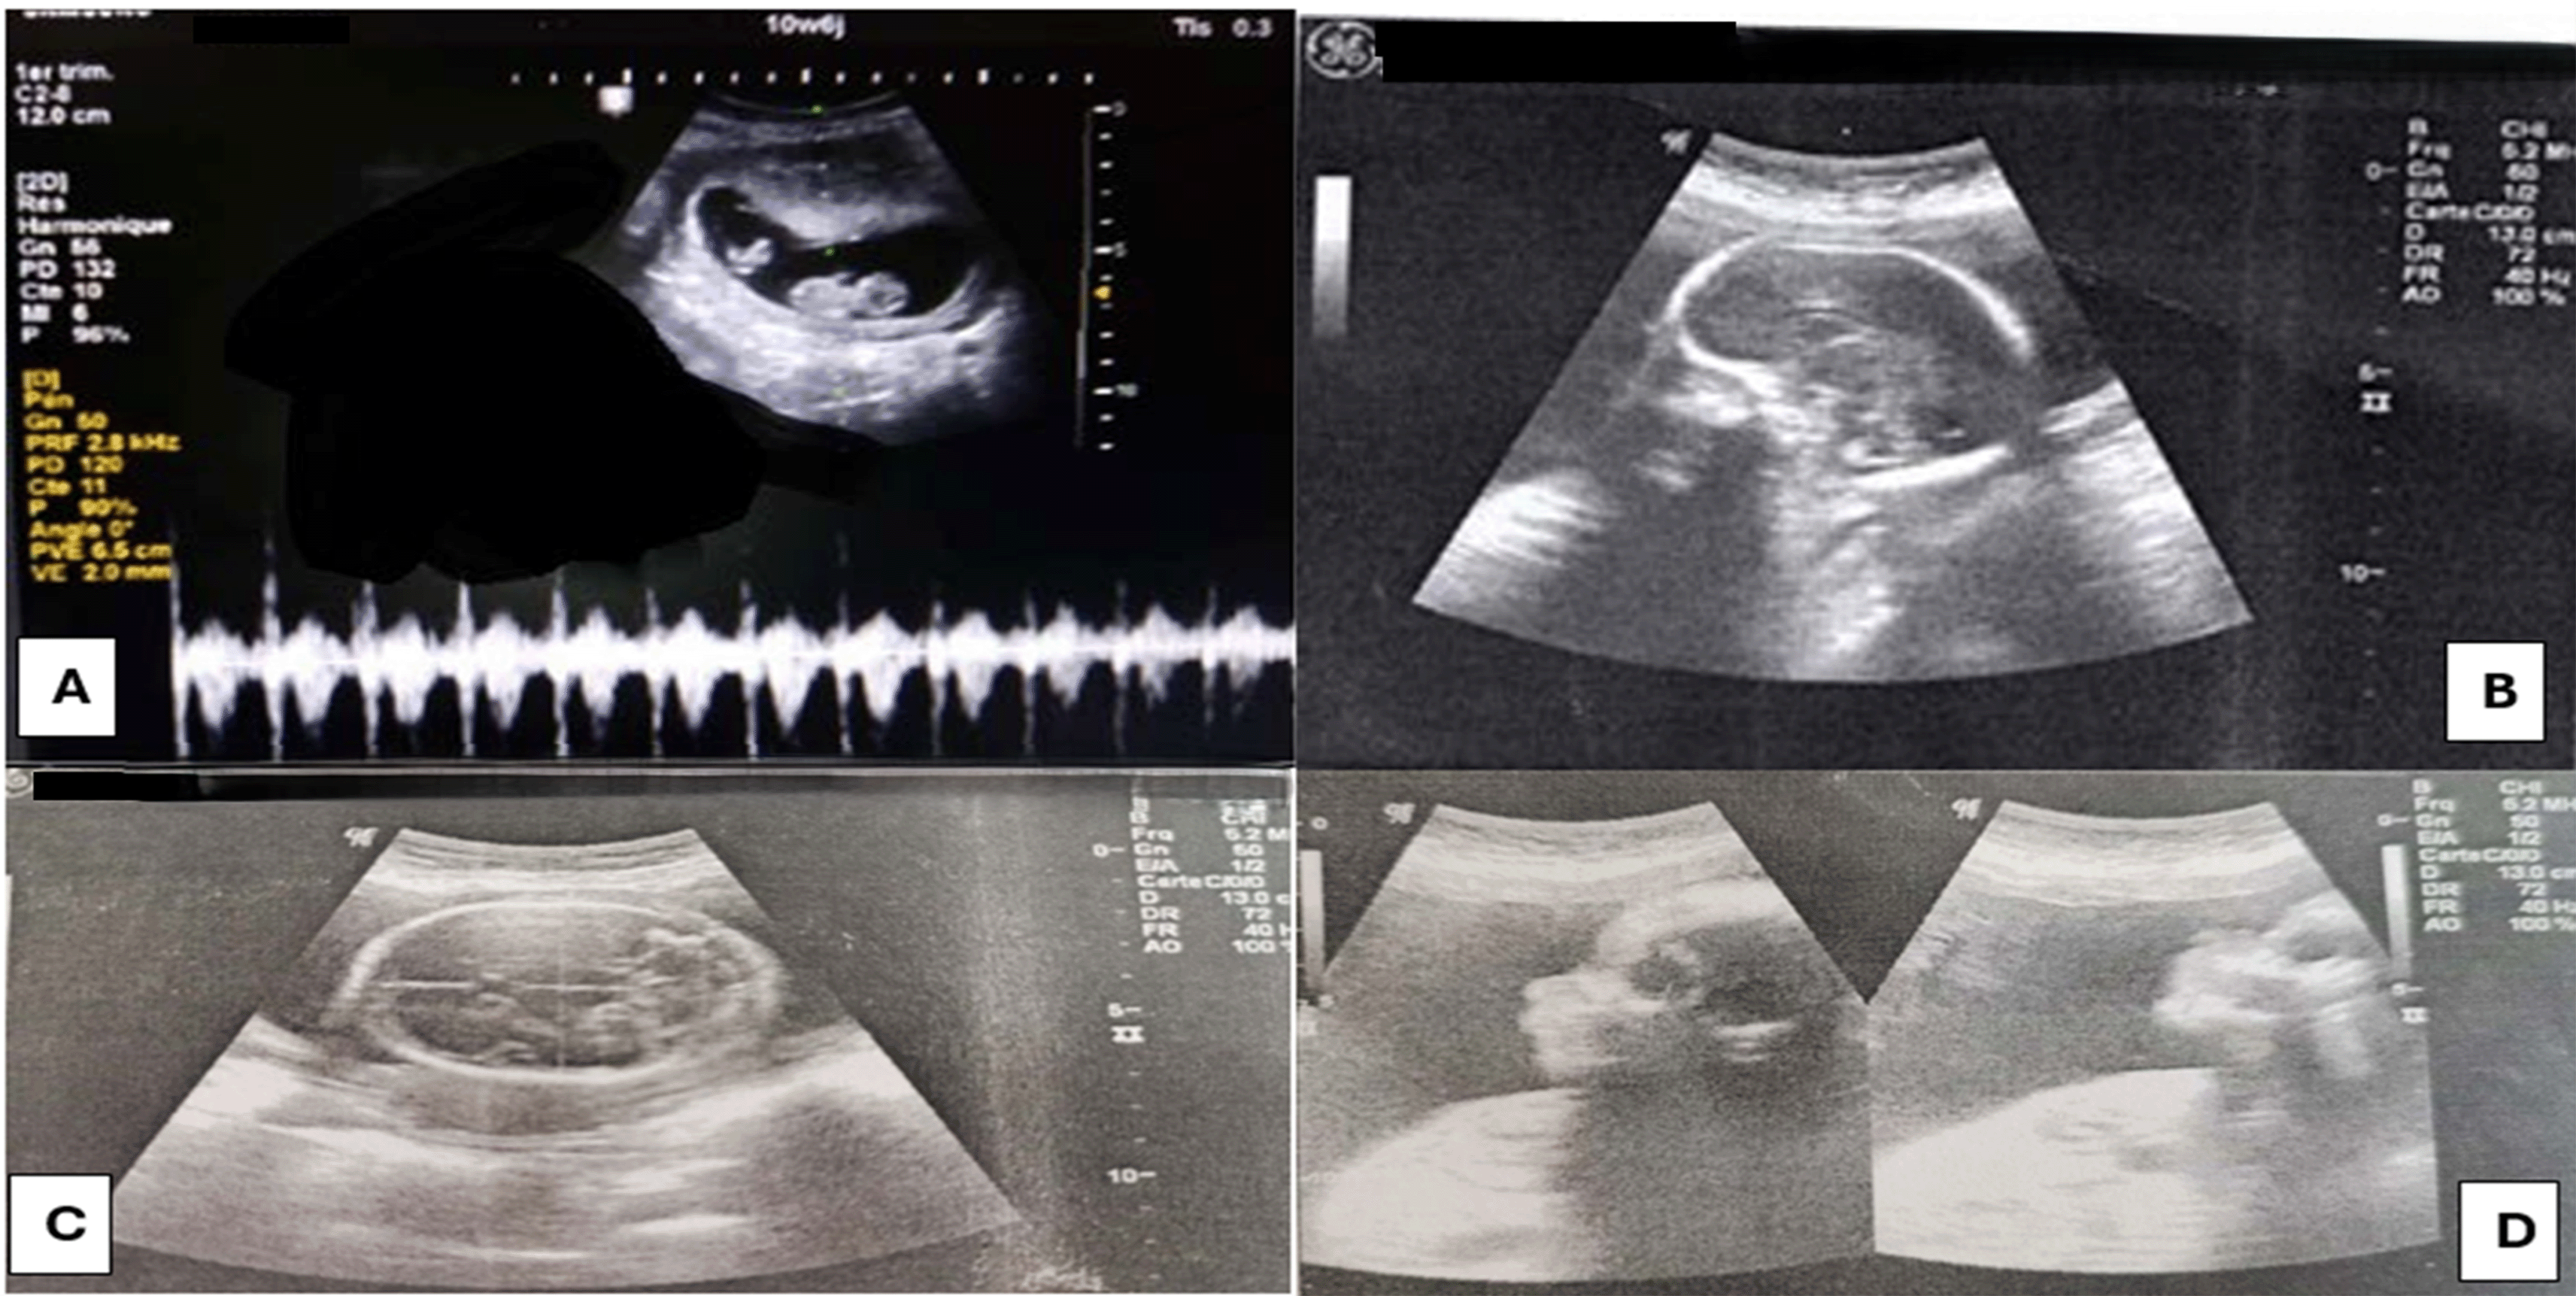

The first ultrasound was performed at 11 weeks by her gynecologist and showed a monochorionic monoamniotic twin pregnancy. The first twin had a normal morphology and cardiac activity, while the second twin had no cardiac activity ( Figure 1)

At 23 weeks an ultrasound check was carried out and showed:

⢠For the First twin: A healthy female fetus with measurements coherent with the presumed age of pregnancy without stunted growth. There were no visible malformations at this age ( Figure 1).

For the second twin: The acardiac monster shows: ( Figure 2)

⢠Alobar holoprosencephaly with thalamic fusion and a very large single ventricle without visible hemispherical parenchyma.

⢠Very large occipital meningocele.

⢠Absence of the upper limbs from the shoulder girdle.

⢠The lower limbs are present in their three segments.

⢠An important and diffuse thickening of the subcutaneous tissue.

⢠Very large cord cyst at the anterior wall of the trunk.

⢠The flow of the umbilical arteries appears reversed.

⢠The quantity of amniotic fluid is normal.